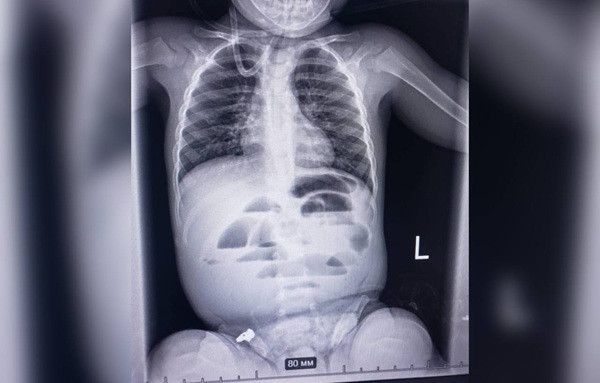

Ситуация неоднозначная: по одним инфекциям регион демонстрирует образцовые показатели, по другим — заметно отстает от общеукраинского уровня.Читайте НН в Telegram: только важные новостиГде лидируем?Николаевский областной центр контроля и профилактики болезней опубликовал свежие данные по охвату населения прививками.Настоящий прорыв область показала в защите детей от полиомиелита. В возрасте 6 лет в нашем регионе привито 99,9% детей, что значительно выше среднего показателя по стране (74,5%).